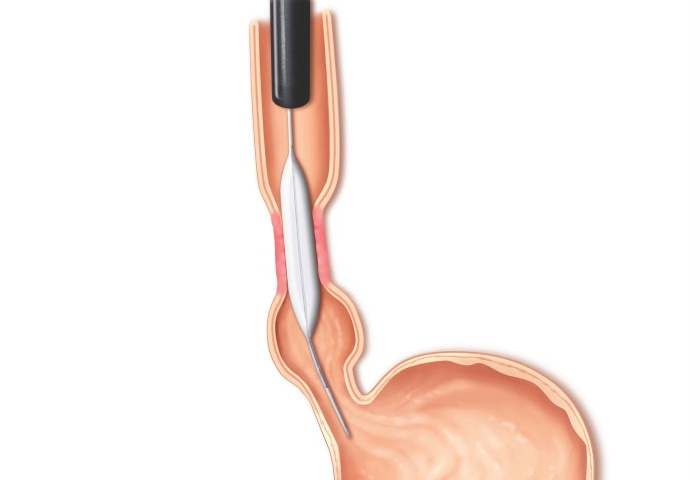

Pacientes que têm o objetivo de emagrecer, podem ter como alternativa a passagem de um balão intragástrico. A passagem do balão é realizada por endoscopia e o procedimento dura cerca de 20 a 30 minutos.

Passagem de Balão Intragástrico

1. O balão intragástrico é introduzido desinsuflado durante a endoscopia e colocado no estômago.

2. Um líquido azul (azul de metileno diluído em soro fisiológico) é colocado dentro do balão através de uma válvula. O volume varia entre 500-700 ml.

3. O aparelho de endoscopia é removido e o balão intragástrico pode ser deixado por um período de até 6 meses.

Como funciona o balão intragástrico?

O balão intragástrico ocupa um espaço dentro do estômago e o paciente fica com sensação de plenitude e saciedade precoce. Em outras palavras, sobra menos espaço para os alimentos, diminuindo o volume ingerido nas refeições.

Pacientes que têm o objetivo de emagrecer, podem ter como alternativa a passagem de um balão intragástrico. A passagem do balão é realizada por endoscopia e o procedimento dura cerca de 20 a 30 minutos.

Passagem de Balão Intragástrico

1. O balão intragástrico é introduzido desinsuflado durante a endoscopia e colocado no estômago.

2. Um líquido azul (azul de metileno diluído em soro fisiológico) é colocado dentro do balão através de uma válvula. O volume varia entre 500-700 ml.

3. O aparelho de endoscopia é removido e o balão intragástrico pode ser deixado por um período de até 6 meses.

Como funciona o balão intragástrico?

O balão intragástrico ocupa um espaço dentro do estômago e o paciente fica com sensação de plenitude e saciedade precoce. Em outras palavras, sobra menos espaço para os alimentos, diminuindo o volume ingerido nas refeições.